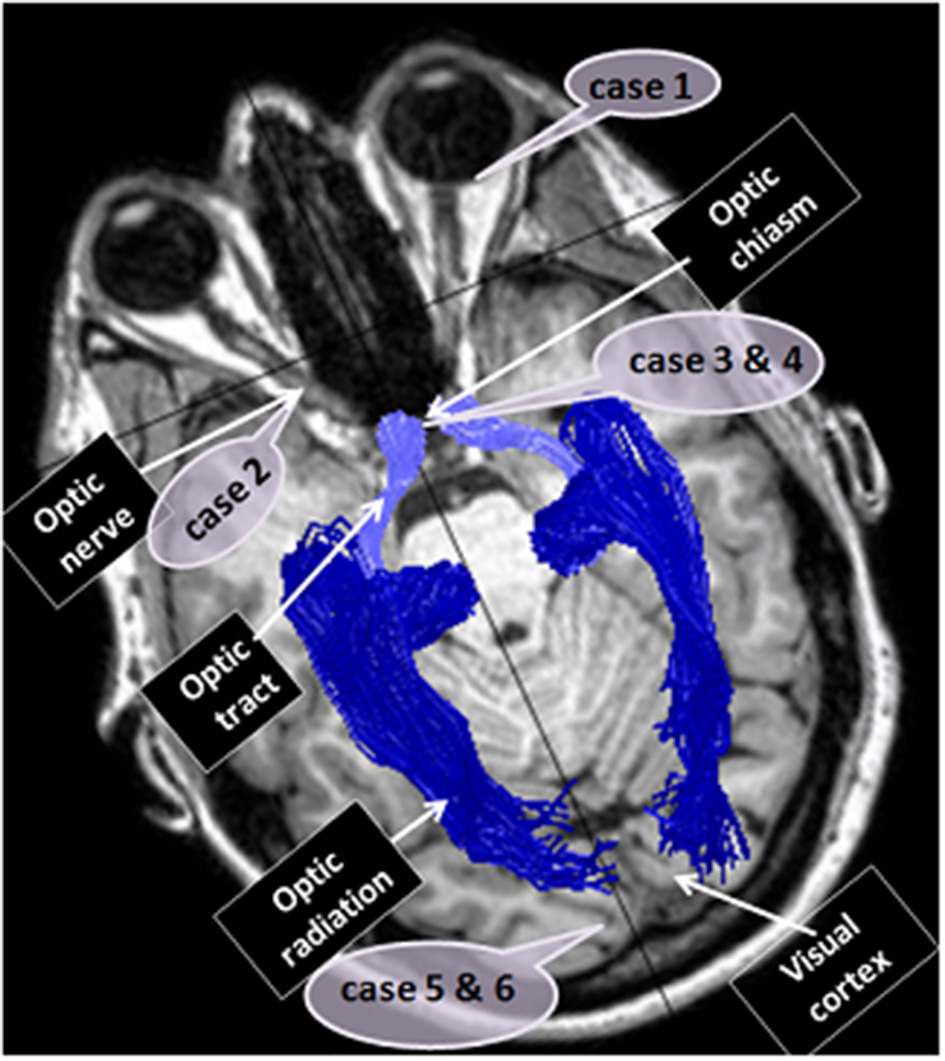

Visual perception is dependent on functioning of the visual system in its entirety and perception may be impaired by damage to any of the pathway's components, starting at the eye itself, through the visual pathways and continuing to the visual processing site, the cortex. Herein we will briefly review examples of different insults along the visual system that we have encountered in patients who have presented during recent years, and their clinical and imaging manifestations (Figure 4).

Figure 4

Case reports localizations. The figure localizes the sites of dysfunction in the different cases reported: case 1—the eye, case 2—the optic nerve, cases 3 and 4—optic chiasm, cases 5 and 6—the visual cortex.